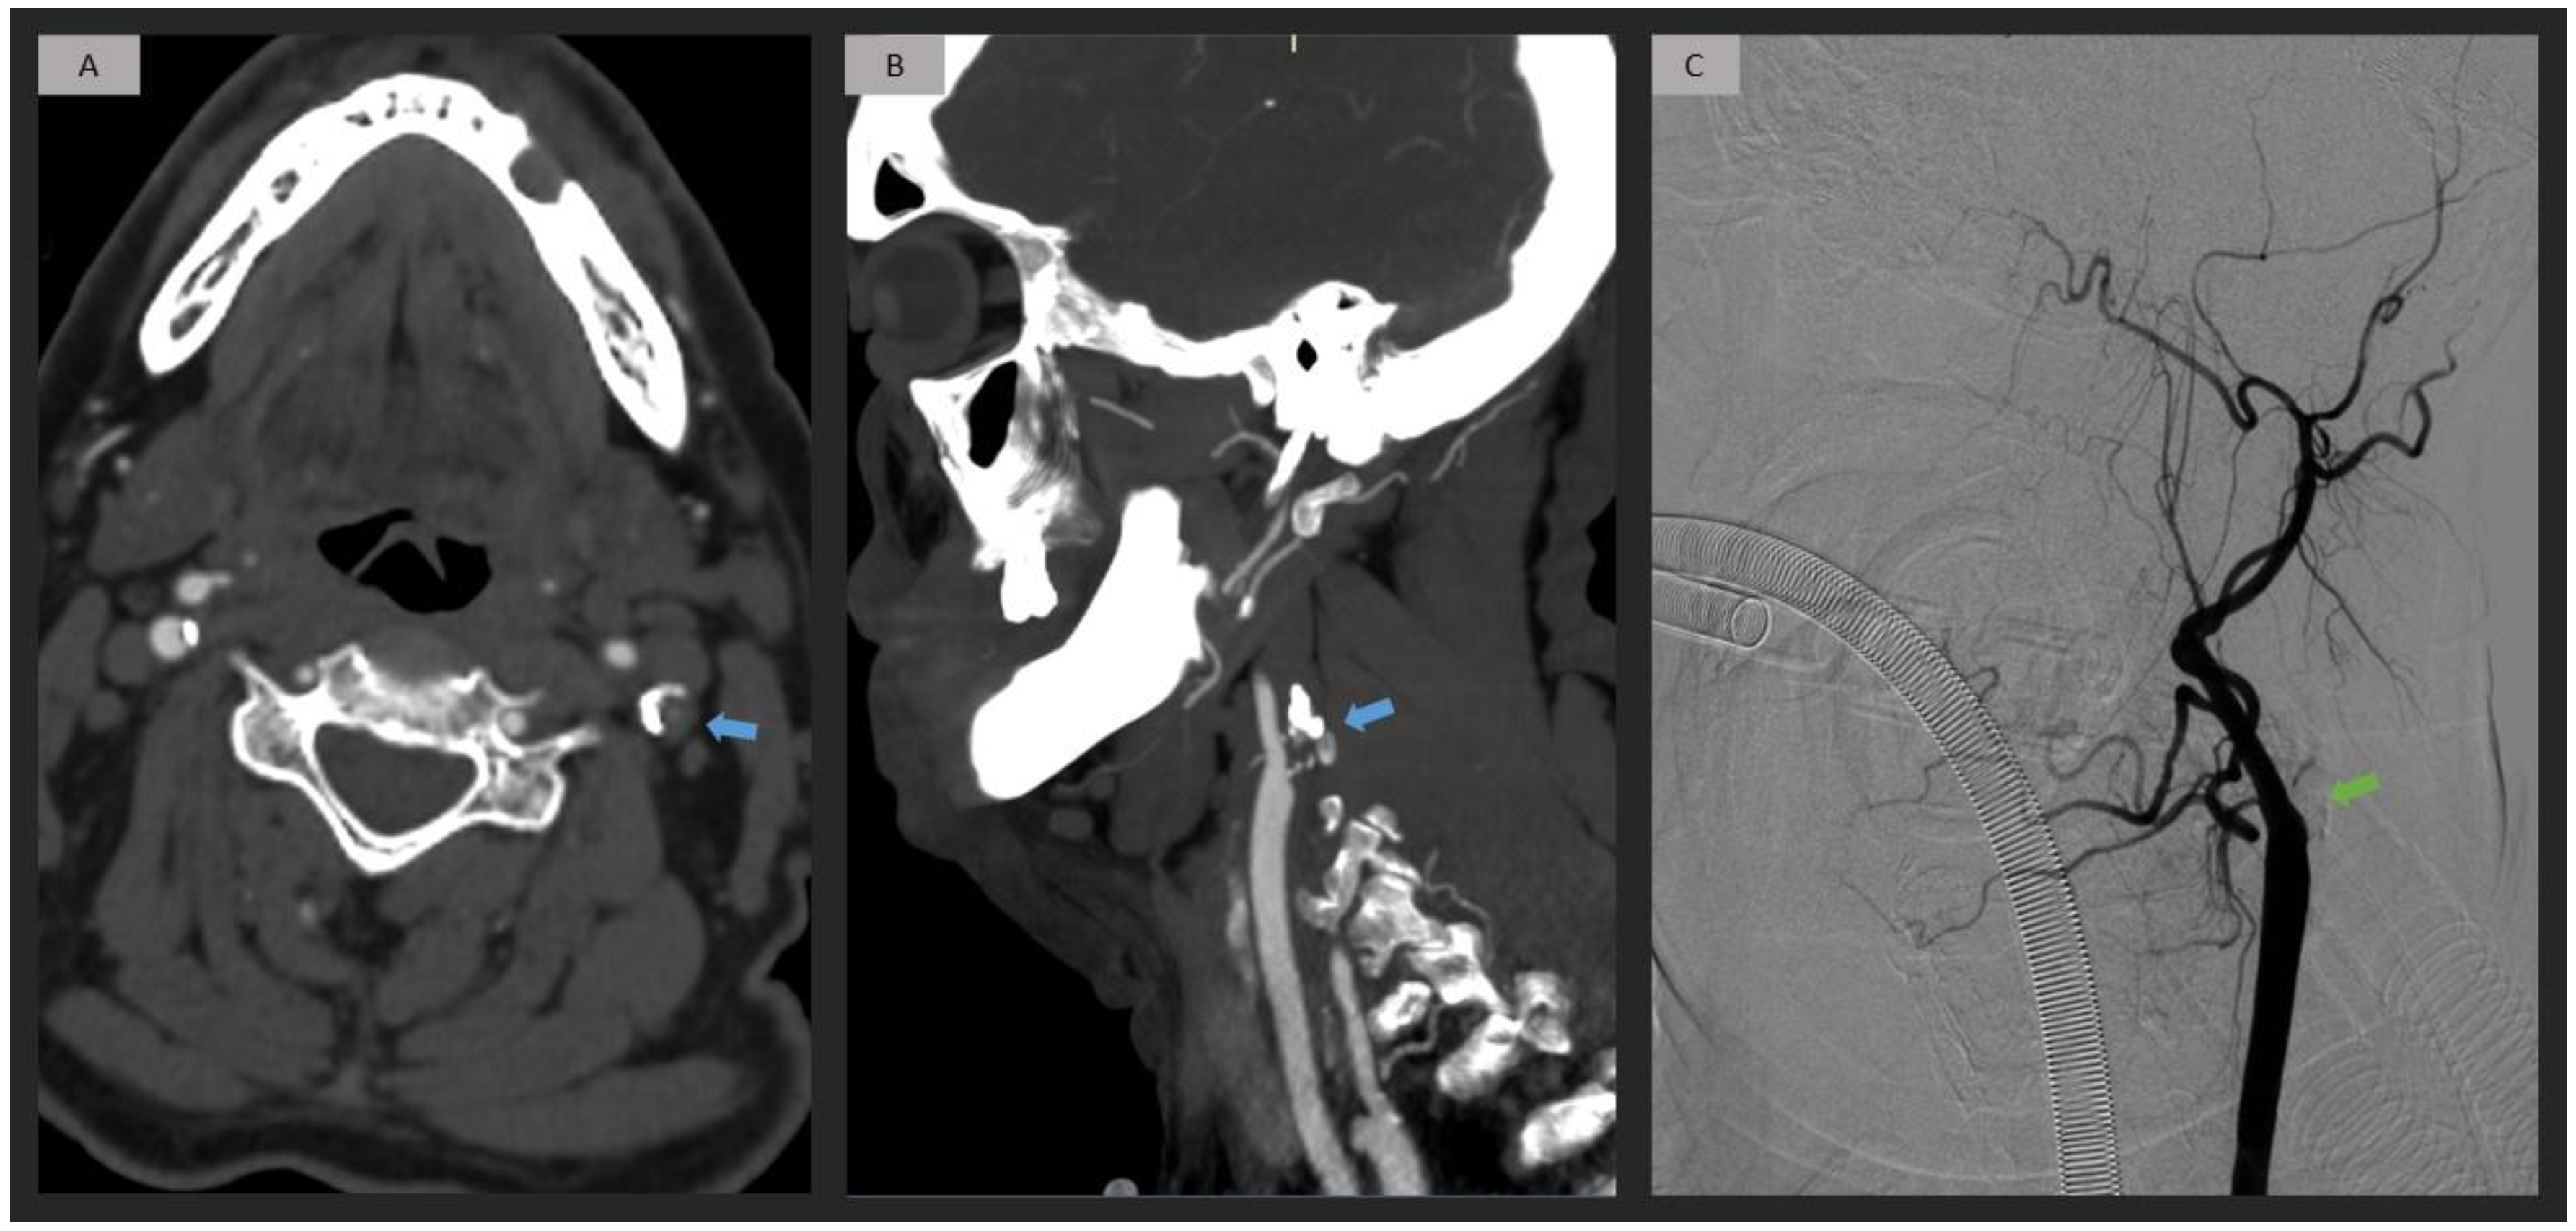

Figure 3.

Patient with left origin ICA occlusion attributed to an atherosclerotic plaque. Axial and sagittal CTA images (A,B) exhibit a well-delimited occlusion at the origin of the ICA, resulting from an atherosclerotic plaque with calcifications (blue arrow). DSA confirms the occlusion of the ICA from its origin (green arrow). (C). ICA = internal carotid artery; CTA = computed tomography angiography; DSA = digital subtraction angiography.